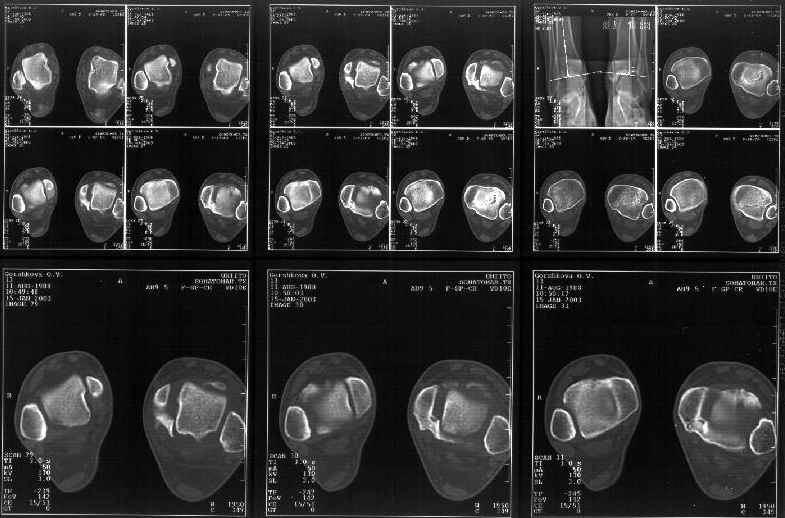

Отправитель: Alexander Chelnokov 19 Январь 2003, 22:34

> К сожалению на последних присланных срезах КТ нет более низкого, через

> таран, среза, который был на прежнем майле. На XR я попытался показать

Сегодня пациентке сделали сравнительную КТ. А ксиальные и Фронтальные срезы приложены. Ваше мнение?

Фронтальные

Аксиальные

Отправитель: Й. Воск 19 Январь 2003, 22:37

Спасибо за КТ -она изумительная. К сожалению, я по дороге на врачебный викенд на Мёртвом море и не смогу подготовить комментарий и схемку до 19.01.03 Помоему, результат КТ даёт чёткую возможность красивой и эффективной помощи.

Отправитель: Й. Воск 19 Январь 2003, 22:50

На КТ я попытался изобразить скромными своими способностями (А)- место перелома, (С)- нормальный суставной зазор меж тараном и тремя его маллеолами. (В)- образовавшийся в результате перелома широкий раза в три зазор, позволяющий, по-моему, сублюксацию тарана при ходьбе. В свете данных КТ, критически важных, я бы предложил вертикальную остеотомию места перелома

задне-внутренним подходом и фиксацию мед. маллеола прижатым к тарану с помощью тонкого compression screw. После этого гипсовый сапожок и немедленное расхаживание ноги.